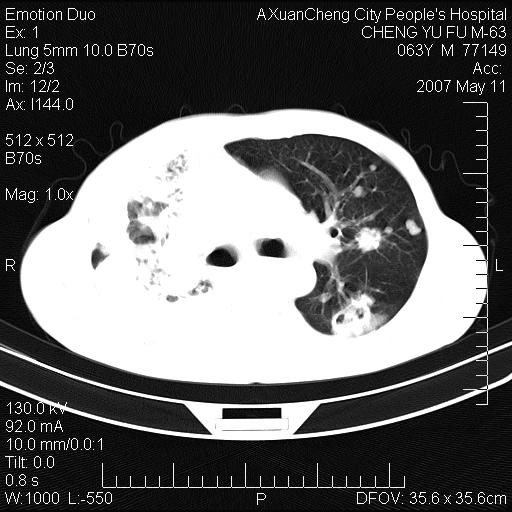

以下是引用小初学者在2007-5-11 19:32:00的发言:[br]1、首先考虑干酪性肺炎支气管播散[br]2、支气管肺泡癌待排

以下是引用zhangzhongshou在2007-5-11 19:30:00的发言:[br]细支气管肺泡癌可能性大。